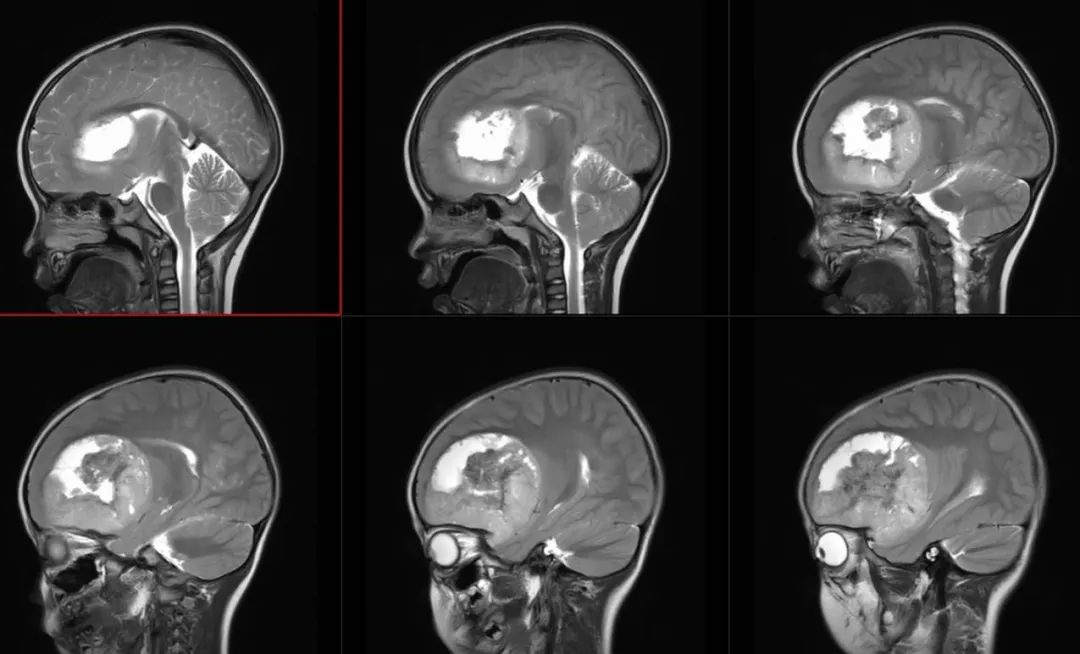

术前影像

术前T2矢状位